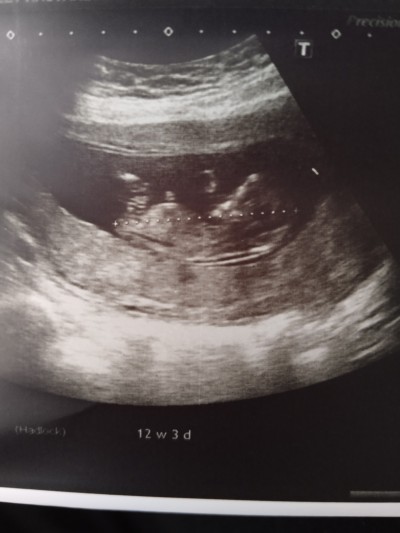

Anlayan var mı acaba cinsiyet konusunda

12+2

İki bacağın ortasında görünen çıkıntı şayet göbek kordonu değilse erkek gibi görünüyor